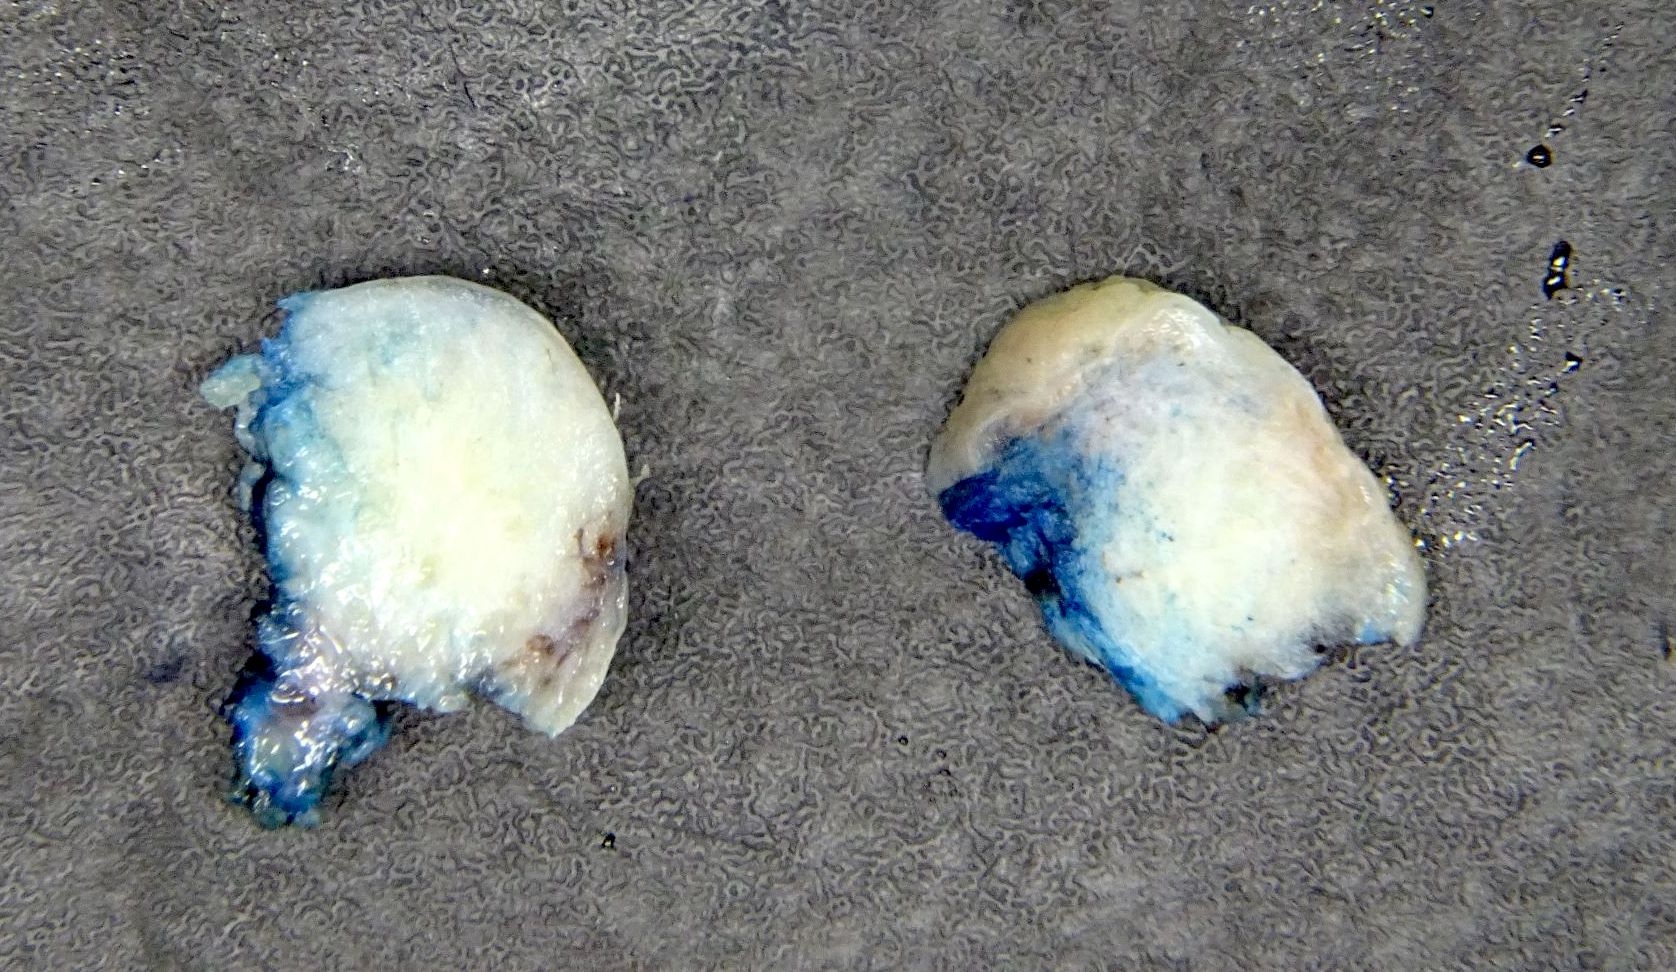

Gross description

- Polypoid, covered by thin, hairless skin

- Can be small (< 2 cm) up to very large

Gross images